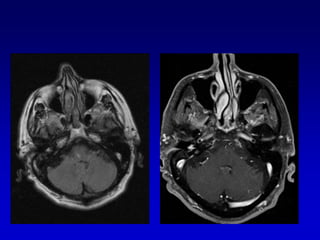

carcinomatosis

hiperemia